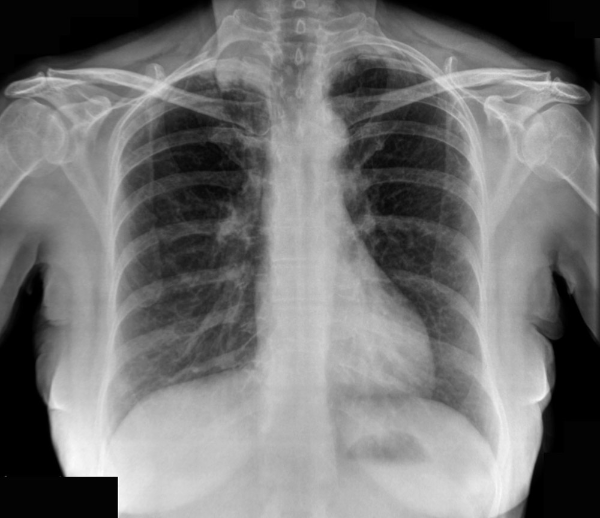

What is shown?

What is the most likely cause?

Miliary nodular lung densities - multiple nodules (1-2mm in size) throughout both lungs with patchy consolidation in left lower zone. TB is the most lilkey cause of this.